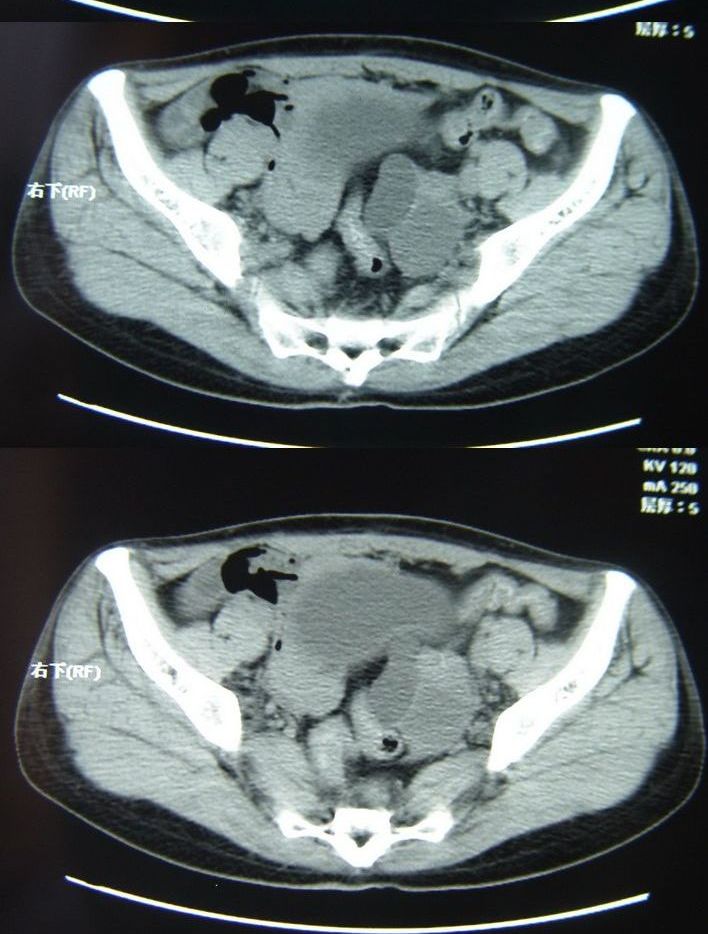

以下是今天的增强片,大家可以看看:

右髂骨见一类圆形略高密度区,似见分层,骨质破坏不明显

考虑良性病变,以动脉瘤样骨囊肿可能性大

右侧髂骨后缘囊状膨胀性骨质改变,无明显骨间隔,周围无明显硬化及骨膜反应,周围软组织无异常,相邻骨组织密度增高,考虑:动脉瘤样骨囊肿可能,要注意与骨巨细胞瘤及转移瘤鉴别。

右侧髂骨膨胀性骨质破坏区 囊内密度尚均匀 骨巨细胞瘤可能性大 动脉瘤样骨囊肿不除外 建议mr观察囊内成分明确诊断 左侧附件区包裹性积液

右侧髂后上棘局限性囊状骨质破坏,大部分界清,似见轻度硬化边,内无分格及钙化,病灶上部局部显示模糊。考虑;骨巨细胞瘤可能大,不除外abc。另可见子宫肌瘤术后子宫缺如。

临床和影像学表现:女性患者46岁,有子宫肌瘤手术病史。影像所见可见残余宫颈部分,左右附件未见新生物;右髂骨翼后端囊状膨胀性骨破坏,囊性部分感觉有强化(楼主标上增强前后的ct值就很好了),未见明确的液—液平面,周边硬化不明显或轻度硬化。

分析:患者年龄46岁,没有明确外伤病史,病变呈膨胀性骨破坏,囊性部分未见明确的液—液平面,周边硬化不明显。综合分析该病例比较符合骨巨细胞瘤,不太符合动脉瘤样骨囊肿。

诊断:1、首先考虑骨巨细胞瘤;2子宫肌瘤术后改变